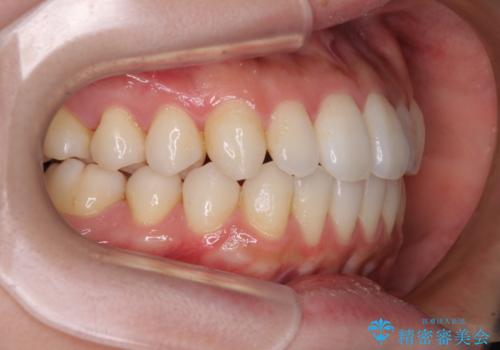

インビザラインで口を閉じやすく

- 下唇に上の前歯が当たることを気にして来院された患者様です。

上顎の親知らずを抜去し、歯列全体を後方に移動させるとともに、IPR(歯と歯の間を削る)を行うことで口元の閉じにくさを改善していくこととしました。

咬合力が強く、マウスピースを介した咬み込みが顕著であったため、奥歯の咬みにくさやIPRのスペースが改善しにくく、治療期間が思った以上にかかってしまいました。